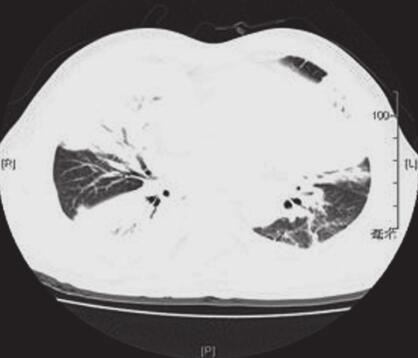

给予甲泼尼龙(80mg,每12小时1次,d1~7,80mg,1次/日,d8~9)抗炎、亚胺培南西司他汀抗感染治疗。患者胸闷、气促缓解,咳嗽消失。2012年3月12日复查血常规示:白细胞8.9×109/L,N% 58.8%。胸部CT(图3):病变较前明显吸收。患者病情好转出院,回家继续口服泼尼龙15mg,2次/日,3个月后停用,现随访一般情况可。

图3 2012年3月12日复查胸部CT示两肺病变较前明显吸收